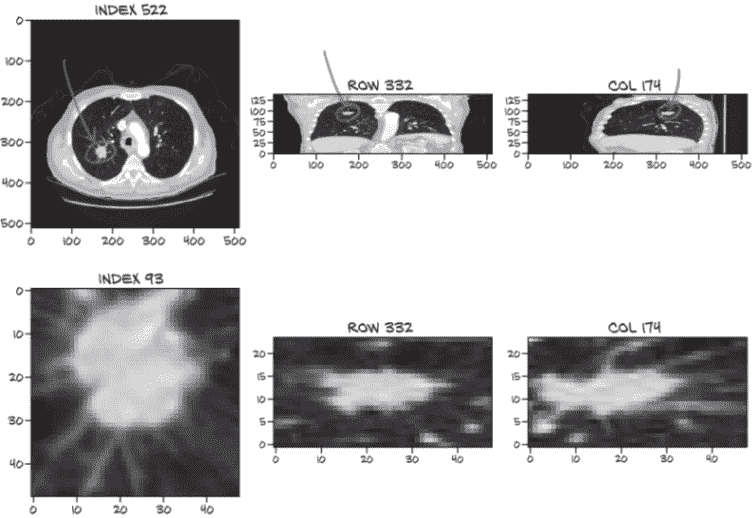

在图 9.8 中,我们可以看到一个恶性结节的典型例子。我们关注的最小结节直径仅几毫米,尽管图 9.8 中的结节较大。正如我们在本章前面讨论的那样,这使得最小结节大约比整个 CT 扫描小一百万倍。患者检测到的结节中超过一半不是恶性的。

图 9.8 一张显示恶性结节与其他结节视觉差异的 CT 扫描